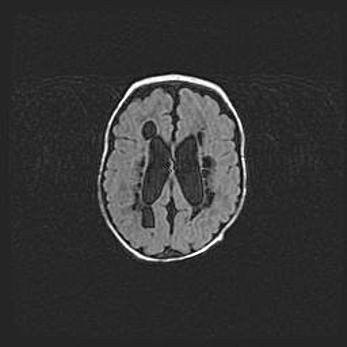

Церебральная ишемия II.

Возраст: 5 дней

Вес: 3400 г

Пол: женский

Окружность головы: 35 см

Срок гестации: 39 недель

Церебральная ишемия – это заболевание, характеризующееся недостаточностью (гипоксией) либо полным прекращением (аноксией) снабжения мозга кислородом по причине закупорки одного или нескольких сосудов. Это приводит к  что метаболическим расстройствам различной степени тяжести в тканях головного мозга, развитию коагуляционных некрозов и гибели нейронов.